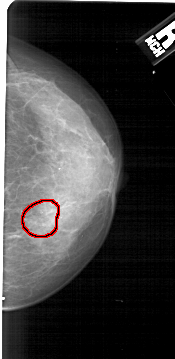

A_1431_1.RIGHT_MLO

RIGHT_MLO LINES 5491 PIXELS_PER_LINE 2611 BITS_PER_PIXEL 12 RESOLUTION 43.5 OVERLAY

FILE: A_1431_1.RIGHT_MLO.OVERLAY

TOTAL_ABNORMALITIES 1

ABNORMALITY 1

LESION_TYPE CALCIFICATION TYPE AMORPHOUS DISTRIBUTION CLUSTERED

ASSESSMENT 4

SUBTLETY 3

PATHOLOGY BENIGN

TOTAL_OUTLINES 1

BOUNDARY